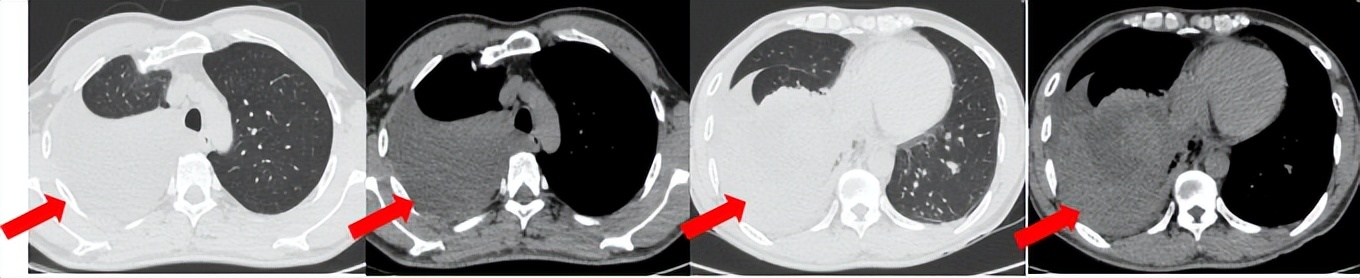

53岁男性,无吸烟饮酒史,脑血栓病史。2024年7月胸部CT:右肺下叶见一团块状软组织密度影,范围约10.8×9.0cm,边界不清,周围并见斑片状磨玻璃密度影,右肺下叶前底段支气管阻塞。纵隔及右肺门见肿大淋巴结影。考虑右肺下叶支气管肺癌。伴纵隔及右肺门淋巴结转移瘤,右下肺静脉瘤栓。2024.7.23行肺穿刺取病理:(肺)腺癌伴有神经内分泌分化。NGS基因检测:RET KIF5B exon15-RET exon12融合。PD-L1(克隆号28-8)TPS=90%。

治疗经过:2024.08开始口服赛普替尼(160mg,bid)。2024.09复查胸CT评效PR。2025.1复查胸CT:右肺下叶外基底段见一不规则形实性肿块,大小约94mm×87mm,边缘呈分叶状,其内密度不匀。右侧胸腔见少许水样密度影。评效PD,PFS=5个月。患者未同意再次组织活检,目前应用卡博替尼治疗,仍在随访中。治疗期间未出现毒性反应。

2024.08

2024.09评效PR

2025.01评效PD